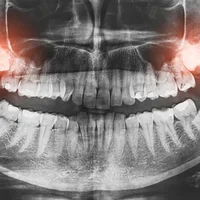

Carie profonde

Anodontie (absence congénitale de dents)